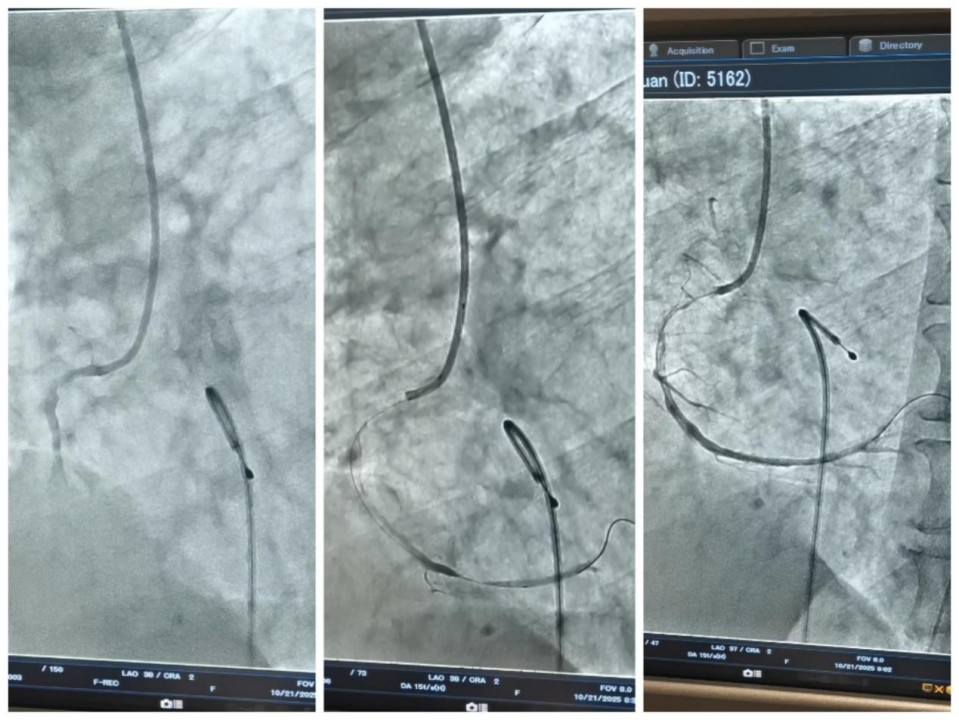

8:06

李大叔被推至介入室准备手术。医护人员启动了 “双保险”生命支持系统:先置入临时心脏起搏器维持心跳,再启用 IABP(主动脉内球囊反搏) 这个人工心脏辅助维持血压和心脏供血。在两大神器的保驾护航下,团队沉着精准地完成冠脉造影,并迅速开通了堵塞的血管。